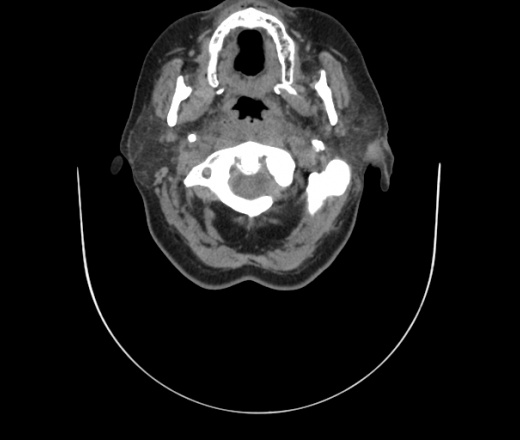

Женщина поступила в х/о спустя 4 дня после того как при употреблении карася подавилась костью.

Наличие газа в средостении на протяжении тел С2-С6 (медиастинальна эмфизема); рыбная кость на уровне тела С6.

При всем уважении, но говорить о медиастинальной эмфиземе, оценивая мягкие ткани шеи, как-то слишком резко. На мой взгляд, это ретрофарингеальное пространство.

Эвакуировали почти 100мл гноя. Но кость не смогли найти. Думаю что она даст дальнейшее ослоднение. Эндоскопически за черпалонадгортаной звязкой не смогли зайти в пищевод, все мягкие ткани отечные, просвет пищевода сдавлен. По всей видимости параэзофагеальная клетчака тоже задействована. Эмпиема, если ее можно так назвать, незнаю как правильно дошла до уровня яремной вырезки. Чем закончиться напишу. Ждем медиастинита.

Флегмона заглоточного пространства шеи, только операция, флегмоны вскрывают. Риск медиастинита.

Согласен с Вами; конечно, наличие газа в клетчатке ретрофарингеального пространства (затмение с опечаткой..). К сожалению, процесс "продвигается" к медиастиниту. Но почему никто, не отмечает наличие рыб. кости; или это для Всех очевидно?

Кость то мы сразу выявили, размеры где то 17*2мм, но ее так и не получается найти в этой каше